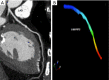

Cardiac CT with iterative reconstructions. (A) Volume rendering; (B) coronary artery tree map; (C,D) multiplanar reconstructions of the coronary arteries.